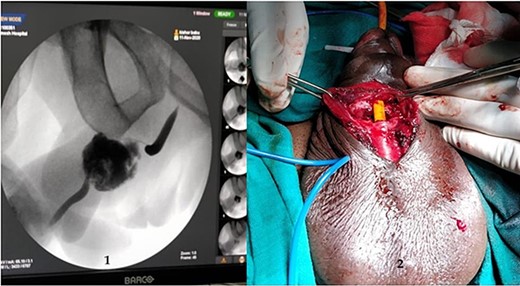

A 37-year-old male presented with a history of a ‘snap’ sound and immediate detumescence of penis during intercourse, when he fell and hit the pubic bone of his partner. There was generalized swelling and pain in the penis. There was acute retention of urine, an attempt to pass a catheter failed and the patient underwent supra-pubic catheterization. On examination, there was classical ‘eggplant deformity’ of the penis with blood at the tip of the meatus. MRI showed a tunical tear on both sides at the penoscrotal junction with indistinct urethra and extensive hematoma in the proximal penile shaft (Fig. 1). With the diagnosis of a fractured penis and possible urethral injury, after proper counselling, the patient was taken up for surgery. On the table, a retrograde urethrogram (RGU) was done showing evidence of partial urethral disruption. On exploration with penoscrotal vertical incision, there was total transection of proximal penile urethra, and a 1.5 cm tunical injury of corpus cavernosum on both sides ventrally (Fig. 2). There was extensive hematoma. Corpora sutured with 4.0 prolene after reconstructing the midline septum. Urethral ends mobilized and anastomosed with 3.0 vicryl in a single layer with minimal spatulation (Fig. 3). The patient was discharged on the 5th post-operative day; Foley catheter was removed on day 21. Follow-up RGU done after 3 months showed no evidence of stricture (Fig. 4).

Follow-up RGU done after 3 months showing no evidence of stricture.